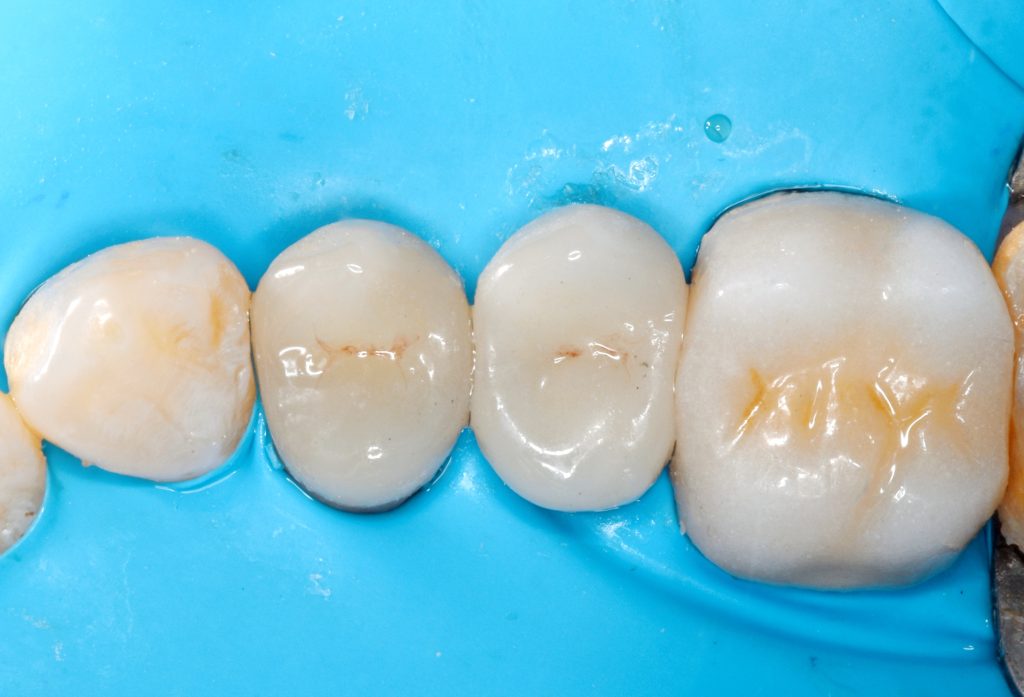

Rubber dam isolation is mandatory in such cases

Caries removal with aid of caries detector dye